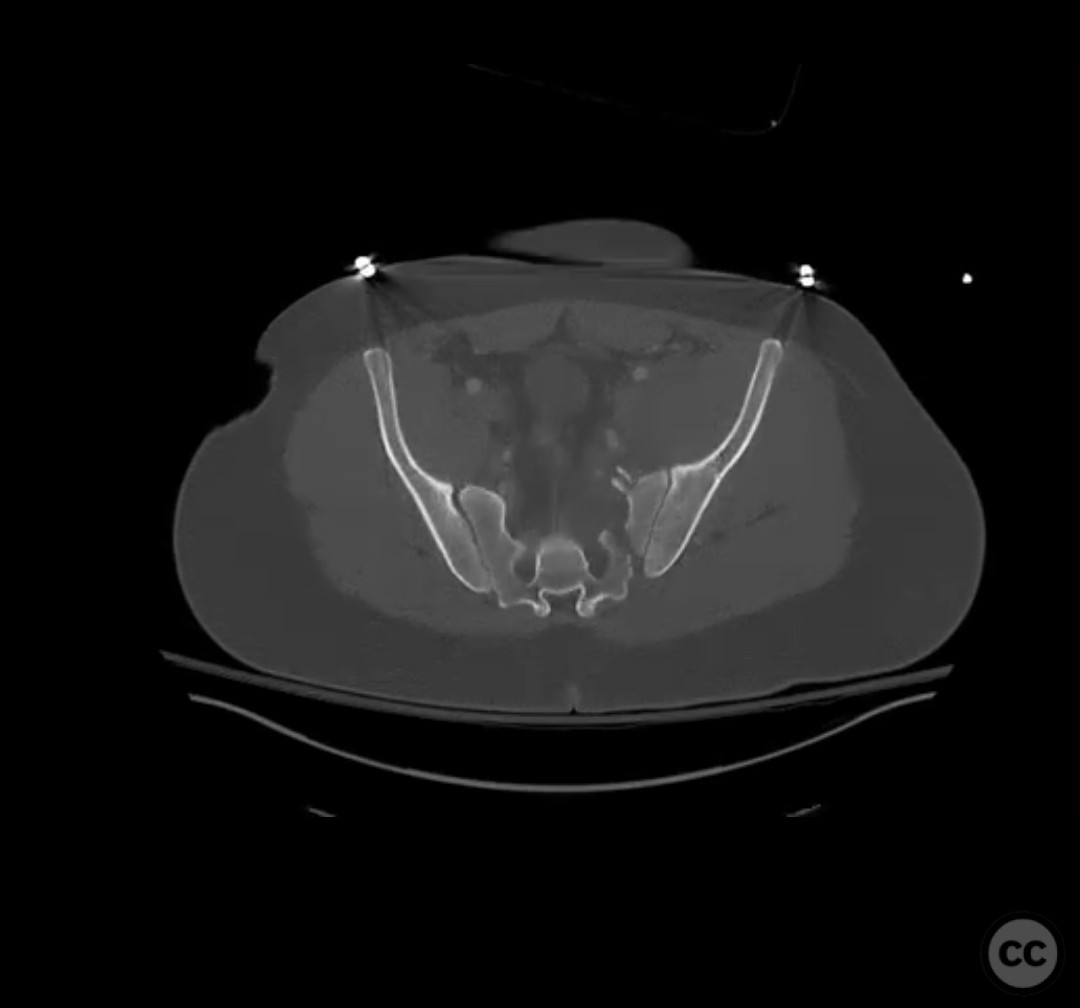

Clinical and radiological findings:  The patient presented with a highly unstable pelvic ring injury and a transverse acetabulum fracture, accompanied by a bladder injury. The bladder injury was addressed emergently with a low vertical midline Pfannenstiel incision for repair, followed by the placement of a low right-sided suprapubic catheter. Radiological imaging confirmed the transverse acetabular fracture and disruption of the left sacroiliac joint, along with a displaced sacral fracture.

Patient positioning:  The patient was positioned supine for the initial stage of pelvic ring stabilization.

The surgical team emphasized the importance of achieving an anatomical reduction of the acetabulum while ensuring stable fixation of the pelvic ring. The presence of the suprapubic catheter necessitated careful planning to avoid interference with surgical access and fixation. The decision to prioritize pelvic ring stabilization first was based on providing a stable segment for accurate acetabular reconstruction. Intraoperative challenges included ensuring precise screw trajectory for sacral fracture fixation and managing potential displacement during reduction maneuvers.